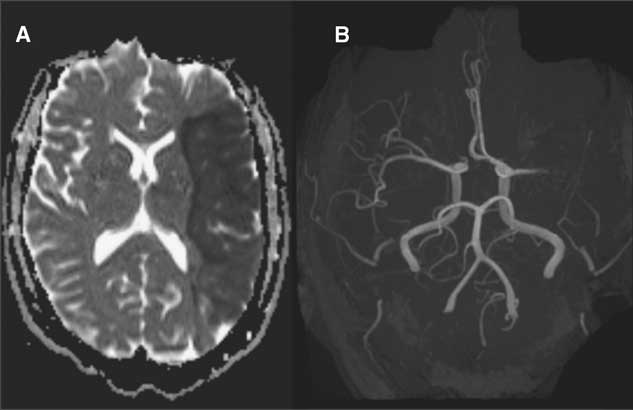

Initial computed tomography (CT) scans demonstrated a thrombosed MCA aneurysm (1.8×1.3×1.0 cm) with associated occlusion of the left MCA at its bifurcation (Figure 1). There was no evidence of subarachnoid hemorrhage or intracerebral blood. There was loss of grey-white differentiation in the left insular, frontal and parietal lobes. The initial Alberta Stroke Program Early CT score was 2, indicating an established stroke with diffuse MCA involvement. As such, stroke mitigation by endovascular or surgical revascularization was not pursued. The next day magnetic resonance imaging (MRI) and MR angiography (MRA) confirmed a large area of ischemic acute infarction in the left MCA territory and extremely poor opacification of distal left MCA branches (Figure 2).

Figure 2 MR sequences demonstrating (A) acute left MCA territory infarction on diffusion weighted imaging (B) and complete occlusion of distal MCA vessels at its bifurcation on MRI time of flight 3-D reconstruction.